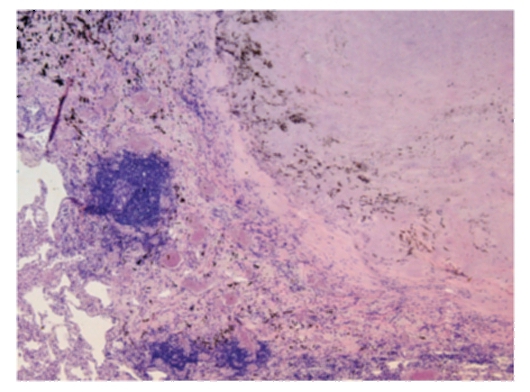

Микроскопический взгляд на мишитарный туберкулез легкого: фотодокументация

Раздел: Снимки-откровения